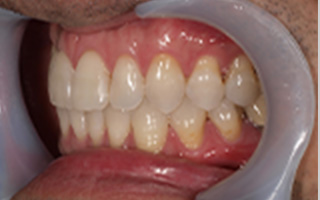

Before

After

| 45歳 男性 | 医療関係者紹介 |

|---|---|

| 主訴 | 右前歯が取れた(右上2) |

| 処置内容 |

1本インプラント埋入+再生療法 抜歯即時埋入⇒抜歯を行い、同時にインプラント埋入(即時埋入) |

| 治療費用 | 上顎: 約40万円(税込) |

| 治療期間 | 約11ヶ月 |

| リスク | 上部構造物、仮歯の破折、術後の腫れ(3日)、人工歯根脱落リスクがあります |